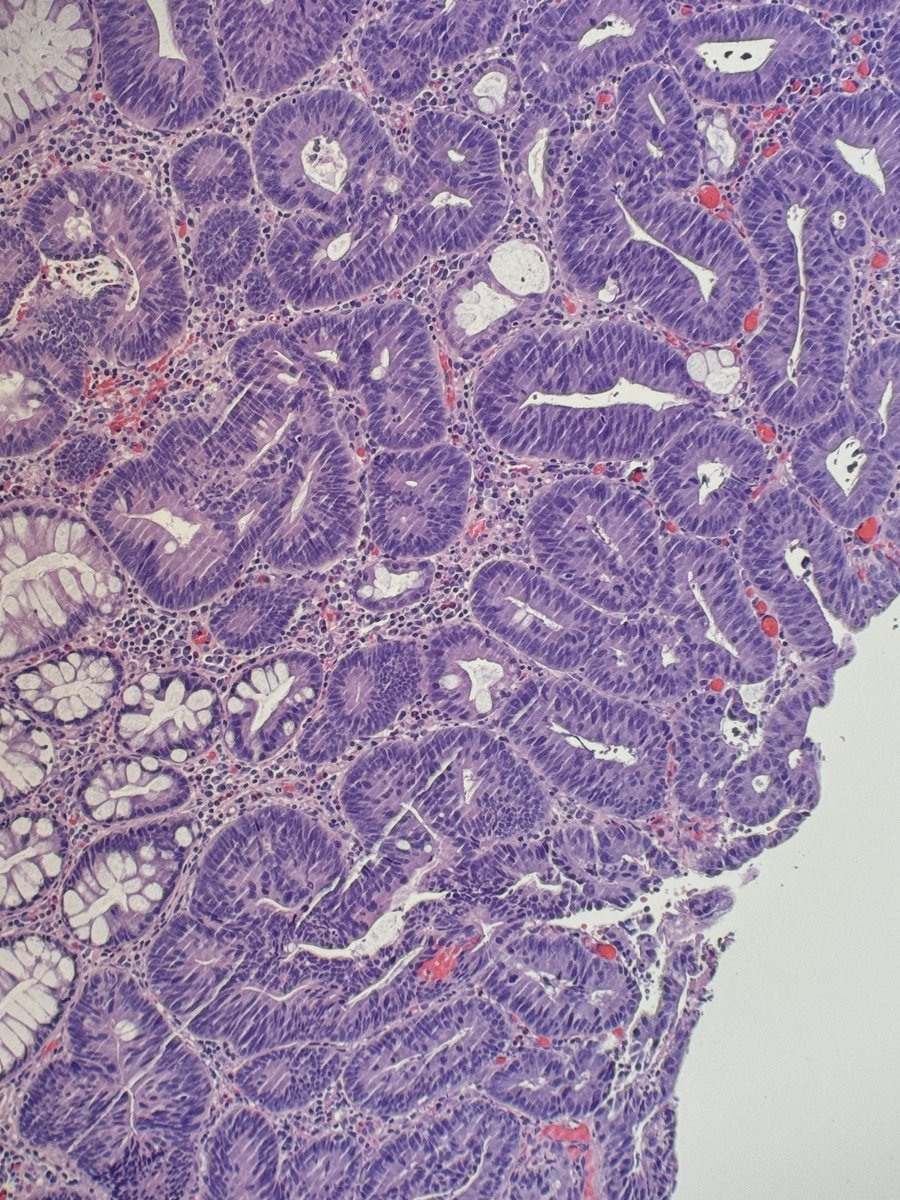

Collision dysplasia: traditional serrated adenoma abutting high‑grade anal intraepithelial neoplasia (AIN 2/3) #pathology #PathTwitter

@Andresangel3 Tubular adenoma with focal high-grade dysplasia

#GIpath #surgpath #Pathology 70 y/o man, rectal polyp. It is a tubular adenoma. High grade dysplasia ?